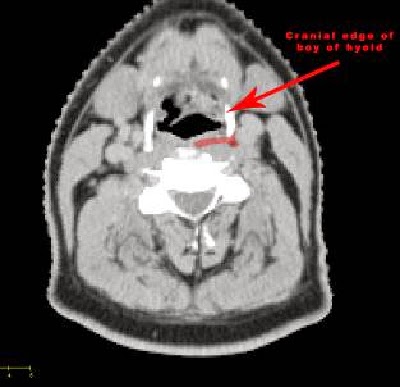

Retropharyngeal lymph nodes lie within the retropharyngeal space, which extends cranially from the base of the skull to the cranial edge of the body of the hyoid bone caudally. Its boundaries are given below.

Caudal: Cranial edge of the body of hyoid bone.